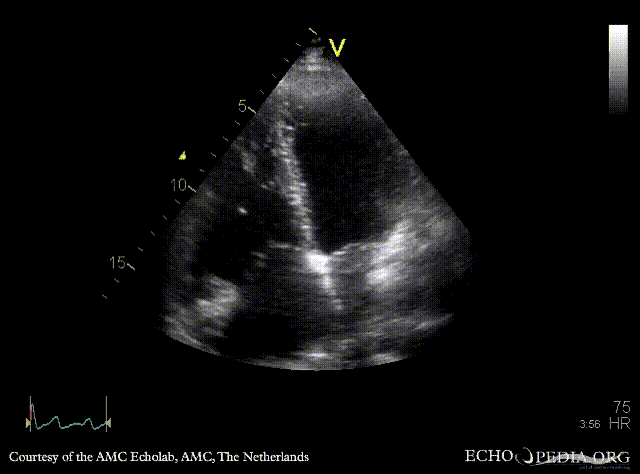

| A4CH: ASD type II | A4CH: enlargement of right ventricle and right atrium |